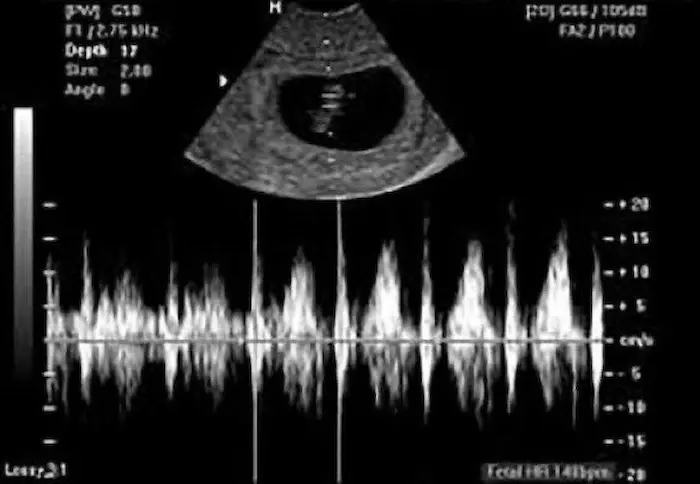

يقيس الطبيب معدل نبض قلب الجنين من خلال عدد النبضات في الدقيقة أثناء الحمل، ويساهم ذلك القياس على تقييم حالة الجنين أثناء زيارات ما قبل الولادة، أو المخاض.

ويتراوح معدل ضربات قلب الجنين الطبيعي بين 110 إلى 160 نبضة في الدقيقة. في المراحل المبكرة جدًا من الحمل يكون حوالي 110 نبضة في الدقيقة.

قد يزداد معدل ضربات قلب الجنين ليصل إلى 170 نبضة في الدقيقة في الأسبوع التاسع تقريبًا، ثم يتباطأ إلى حوالي 110 نبضة في الدقيقة بعد ذلك.

2- مراقبة معدل ضربات قلب الجنين

يستخدم الطبيب جهاز مراقبة معدل ضربات قلب الجنين أثناء المخاض، وذلك للتحقق من وجود أي تغيرات. ويشمل طريقتين

يوضع مسبار الدوبلر على بطن الحامل، وذلك لسماع نبضات الجنين، ويمكن استخدامه بدءًا من الأسبوع العاشر إلى 12 من الحمل.

الفرق بين نبض الجنين ونبض الأم

يعد التمييز بين معدل ضربات قلب الأم، والجنين أمرًا أساسيًا، وذلك لاتخاذ قرارات الرعاية المناسبة. ويكمن الفرق بين نبض قلب الجنين، والأم في السرعة. حيث يعد نبض قلب الجنين سريع مقارنةً بضربات قلب الأم، ويعد المعدل الطبيعي له 110 نبضة في الدقيقة، وقد يصل إلى 160 نبضة في الدقيقة في الثلثين الثاني، والثالث من الحمل.

كما يزداد معدل ضربات قلب الجنين من 140 إلى 170 نبضة في الدقيقة، وذلك بحلول الأسبوع التاسع. بينما يتراوح معدل ضربات قلب الأم بين 60 نبضة إلى 100 نبضة في الدقيقة، ويعد أبطأ، وأكثر انتظامًا.